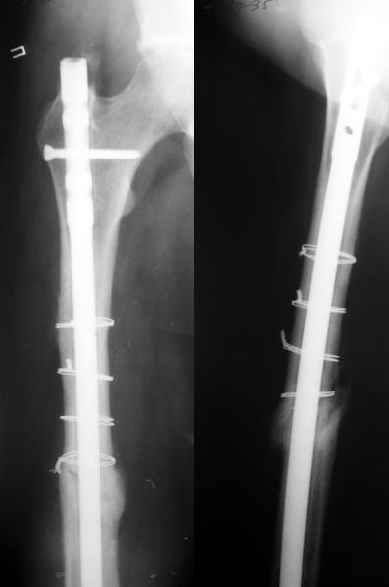

1) Мы бы не убирали проволоку, и вообще не вмешивались открыто на очаге - это ничего не даст, кроме ухудшения кровоснабжения концов отломков. Если просто закрыто перештифтовать при подобной картине, лучше с рассврливанием - это по нашему опыту дает сращение в 100%. В приложении пример - болезненное несращение более года, результат через полгода.

1

2

2)запирающие винты выглядят чрезмерно короткими. А им бы тут надо хорошо держаться за оба кортекса. Это в проксимальном отломке можно ввести было только динамический винт, или вообще винты не вводить.